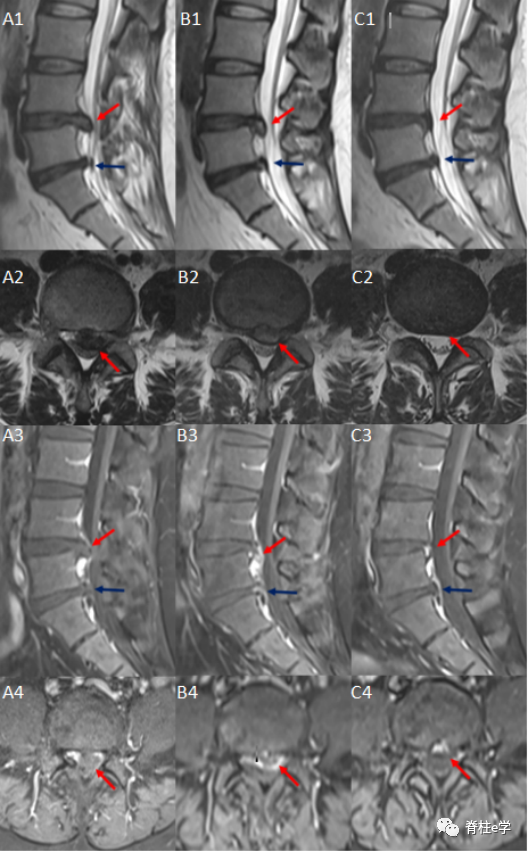

图示MRI:初诊(A)、8个月(B)和18个月(C)

患者女,30岁,腰痛伴双下肢疼痛,无马尾受压症状。查体示:L4/L5和L5/S1双侧棘突压痛放射至双下肢,左侧、右侧直腿抬高试验50°(+)。双下肢皮肤感觉、肌力正常。图示:L4/L5椎间盘突出后再吸收,L5/S1椎间盘前后无变化。腰椎间盘突出后重吸收:是指腰椎间盘突出症患者未经手术治疗而发生的突出髓核消失或缩小的现象。对腰椎间盘突出后重吸收现象的研究,最早可以追溯到1984年,国外学者Guinto通过个案报道分享了一例腰椎间盘突出症患者保守治疗CT随访案例,首次发现突出的椎间盘组织可以缩小或者消失,并称之为“自发性消退”。

MRI对软组织分辨率较高,能清晰显示突出髓核组织的形态、位置、信号特点及神经继发性改变,并可获得多层面、多角度图像。基于MRI显示的椎间盘突出程度预测腰椎间盘突出后重吸收,具有重要意义。目前,由于大部分对突出物体积变化的研究还停留于肉眼对MRI影像的直观感觉,为了精确反映突出物体积的变化。本文推荐国内学者俞鹏飞首创的基于MRI测定腰椎间盘突出物体积及其突出率和吸收率的计算方法:

a:上椎体后缘中点至椎管后壁的长度(椎管直径);

b:从突出物最高点到椎管后壁的距离;

突出率 = [(a-b)/a ] X 100%

在MRI矢状位T2W1图像上,以上位椎体后下缘及下位椎体后上缘连线为内边界,突出物边缘作为外边界,计算突出物体积。

突出物体积 =(层间距 + 层厚)X∑每一层突出物面积,

吸收率 =(治疗前突出物体积-治疗后突出物体积) /治疗前突出物体积X100%